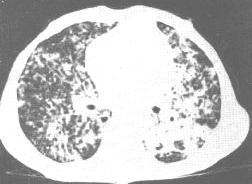

原发于身体其它部位的恶性肿瘤经血道或淋巴道转移到肺的相当多见。据统计在死于恶性肿瘤的病例中约20~30%有肺转移。恶性肿瘤发生肺转移的时间早晚不一,大多数病例在原发癌肿出现后3年内发生转移,亦有长达10年以上者,但也有少数病例肺转移灶比原发肿瘤更早被发现。转移到肺的原发恶性肿瘤多来自乳腺、骨骼、消化道和泌尿生殖系统。

肺转移性肿瘤大多为遍及两侧肺的多发性病灶,大小不一,密度均匀,对这些晚期癌肿病例,目前尚无有效的治疗方法。少数病例肺内只有单个孤立的转移病灶则可考虑外科治疗。

细支气管肺泡细胞癌(腺癌的一种亚型)会使气腔实变,且通常不向肺脏外扩散。尽管可表现为孤立型,但有时可以根据其多发病灶起源与其他类型支气管癌相鉴别。